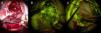

ResultsAll patients presented with long standing headache dating back at least two years. There was no gender predominance in our series. Radiological evaluation revealed two parasagittal and two convexity meningiomas located at the frontal region. Two lesions were located at the tuberculum sellae and the foramen magnum. All of the tumors were totally excised (Simpson Grade I or II). Pathology results included meningothelial meningioma in three patients, angiomatous meningioma in two patients, and metaplastic meningioma in one patient. In two patients, the cystic meningiomas were resected with the use of sodium fluorescein (Na-Fl) under a YELLOW 560nm microscope filter. Na-Fl was found to be very useful in demonstrating the brain–tumor interface, and it was especially effective in resecting the cyst wall of the peritumoural cystic meningiomas. None of the patients had any complications, and no recurrences were noted in any of the patients within the mean follow-up period of 51 months (range: 16–102 months).

ConclusionIt is important to note MRI changes specific to cystic meningioma and include meningiomas in the differential diagnosis of intracranial cystic lesions. The use of sodium fluorescein (Na-Fl) under a YELLOW 560nm microscope filter is a useful tool to differentiate the brain-tumor interface, as well as to identify the cyst wall in order to fully resect the tumor with the cystic component to avoid recurrence and achieve better clinical results.